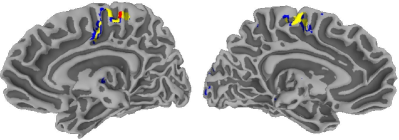

As before, we run the kmsubscript𝑘𝑚k_{m}-means algorithm to termination, with 100pmax(K,10)100𝑝𝐾10100p\max(K,10) initializations using the methods in Section II-C, for K=1,2,,20𝐾1220K=1,2,\ldots,20. The jump statistic identified the three-groups solution as the optimal partitioning. The resulting groups are displayed in Figure 8 separately, for each of the eleven

Refer to caption

(a)

(b)

Figure 8: Regions of activation detected from voxels in eleven replications of an fMRI study.

experiments. The first group (denoted by red) consists of 235 voxels whose average mean Z𝑍Z-score is 10.31, the second (yellow) group has 965 voxels with average mean Z𝑍Z-score 6.83, and the third (blue) group includes 1627 voxels with an average mean Z𝑍Z-score of 4.96. The first group is where the activation is most emphatic and is almost entirely in the right primary motor cortex (M1), the ipsi- and contra-lateral pre-motor cortices (pre-M1), and the supplementary motor cortex (SMA). The other two groups of voxels represent two different kinds of milder activation and are primarily located in the right pre-SMA, and interestingly also in the left M1, pre-M1, and the SMA. This last observation is an interesting finding and is suggestive that activation in a right-hand dominant male is also associated in the left hemisphere of the brain even when it is the non-dominant hand that is active in performing a task. It is important to note that following a whole data strategy in this experiment would not have been able to identify this additional finding because almost all the 156 voxels that have non-thresholded Z𝑍Z-scores for all eleven replications (that is, having no missing values) are in the right hemisphere. Our application here also demonstrates an important approach to amalgamating the results from different fMRI activation studies.